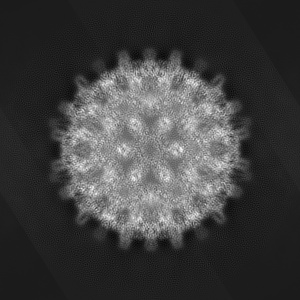

EMD-29858

Single-particle

3.8 Å

Hepatitis B virus capsid bound to importin alpha1

Sample Organism: Hepatitis B virus

Sample: Capsid formed by Cp183 when importin alpha1 is incorporated

Fitted models: 8g8y

Deposition Authors: Yang R , Cingolani G

Structural basis for nuclear import of hepatitis B virus (HBV) nucleocapsid core.

Yang R , Ko YH , Li F , Lokareddy RK, Hou CD , Kim C, Klein S , Antolinez S , Marin JF , Perez-Segura C , Jarrold MF, Zlotnick A , Hadden-Perilla JA , Cingolani G

(2024) Sci Adv , 10 , eadi7606 - eadi7606

PUBMED: 38198557

DOI: doi:10.1126/sciadv.adi7606